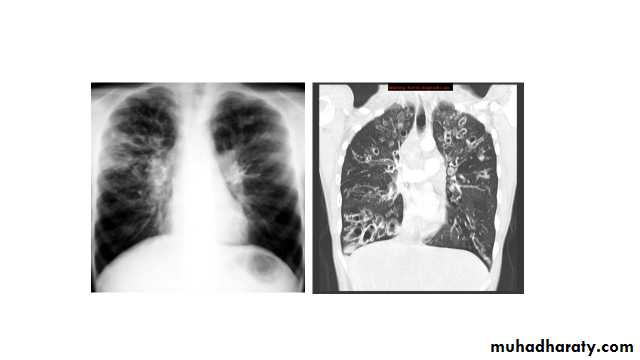

Plain radiograph

Chest x-rays are usually abnormal1. Tram-track opacities are seen in cylindrical bronchiectasis, and

2. air-fluid levels may be seen in cystic bronchiectasis.

Honey comb shadow

3.Overall there appears to be an increase in bronchovascular markings, and bronchi seen end on may appear as ring shadows .

4.Pulmonary vasculature appears ill-defined, thought to represent peri bronchovascular fibrosis .